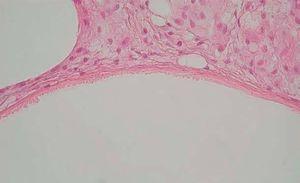

Desde el punto de vista histopatológico, se observó en todos los casos la formación de estructuras membranosas hialinas, eosinófilas, amorfas, anucleares, que revestían espacios quísticos de tamaños variables, localizadas en el interior de los lobulillos del tejido celular subcutáneo. Estos quistes estaban revestidos por una membrana hialina gruesa (fig. 4) o se observaban proyecciones paralelas o en arabesco de membranas hialinas (figs. 5 y 6). También se observó depósito de material lipomembranoso en áreas de fibrosis septal. Las membranas mostraban una intensa positividad con la tinción de PAS y eran diastasa-resistentes. En algunos casos se observaba una reacción granulomatosa alrededor de los espacios quísticos (fig. 7). En uno de los casos se observó un infiltrado neutrofílico en el espesor de la pared de los espacios quísticos (fig. 8), que correspondía a necrosis de adipocitos.

Fig. 4.--HE, x40. Espacios quísticos dimensiones variables revestidos por membrana hialina engrosada.